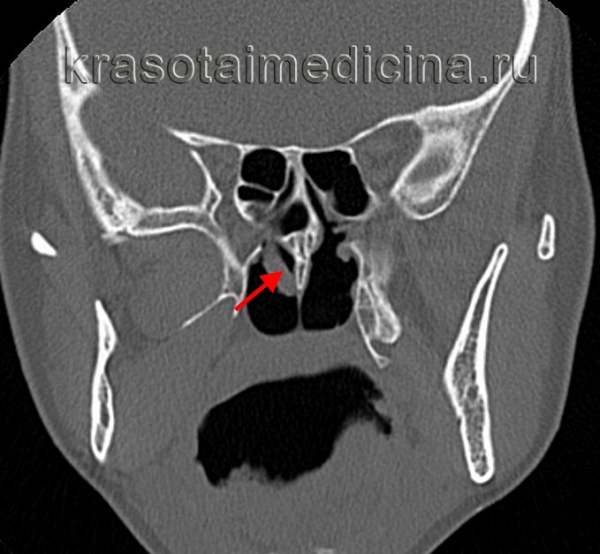

(Слева) При корональной «костной» КТ определяется снижение пневматизации левой верхнечелюстной пазухи, устье которой расширено. Визуализируется большой одиночный полип, пролабирующий через устье в полость носа и приводящий к обструкции среднего носового хода.

(Справа) При сагиттальной МРТ Т1 визуализируется крупный полип ва с промежуточным сигналом, пролабирующий из полости носа в носоглотку. Обратите внимание на нормальный гиперинтенсивный сигнал в небе ниже полипа. Ткань аденоидов слегка гиперинтенсивна по сравнению с полипом.